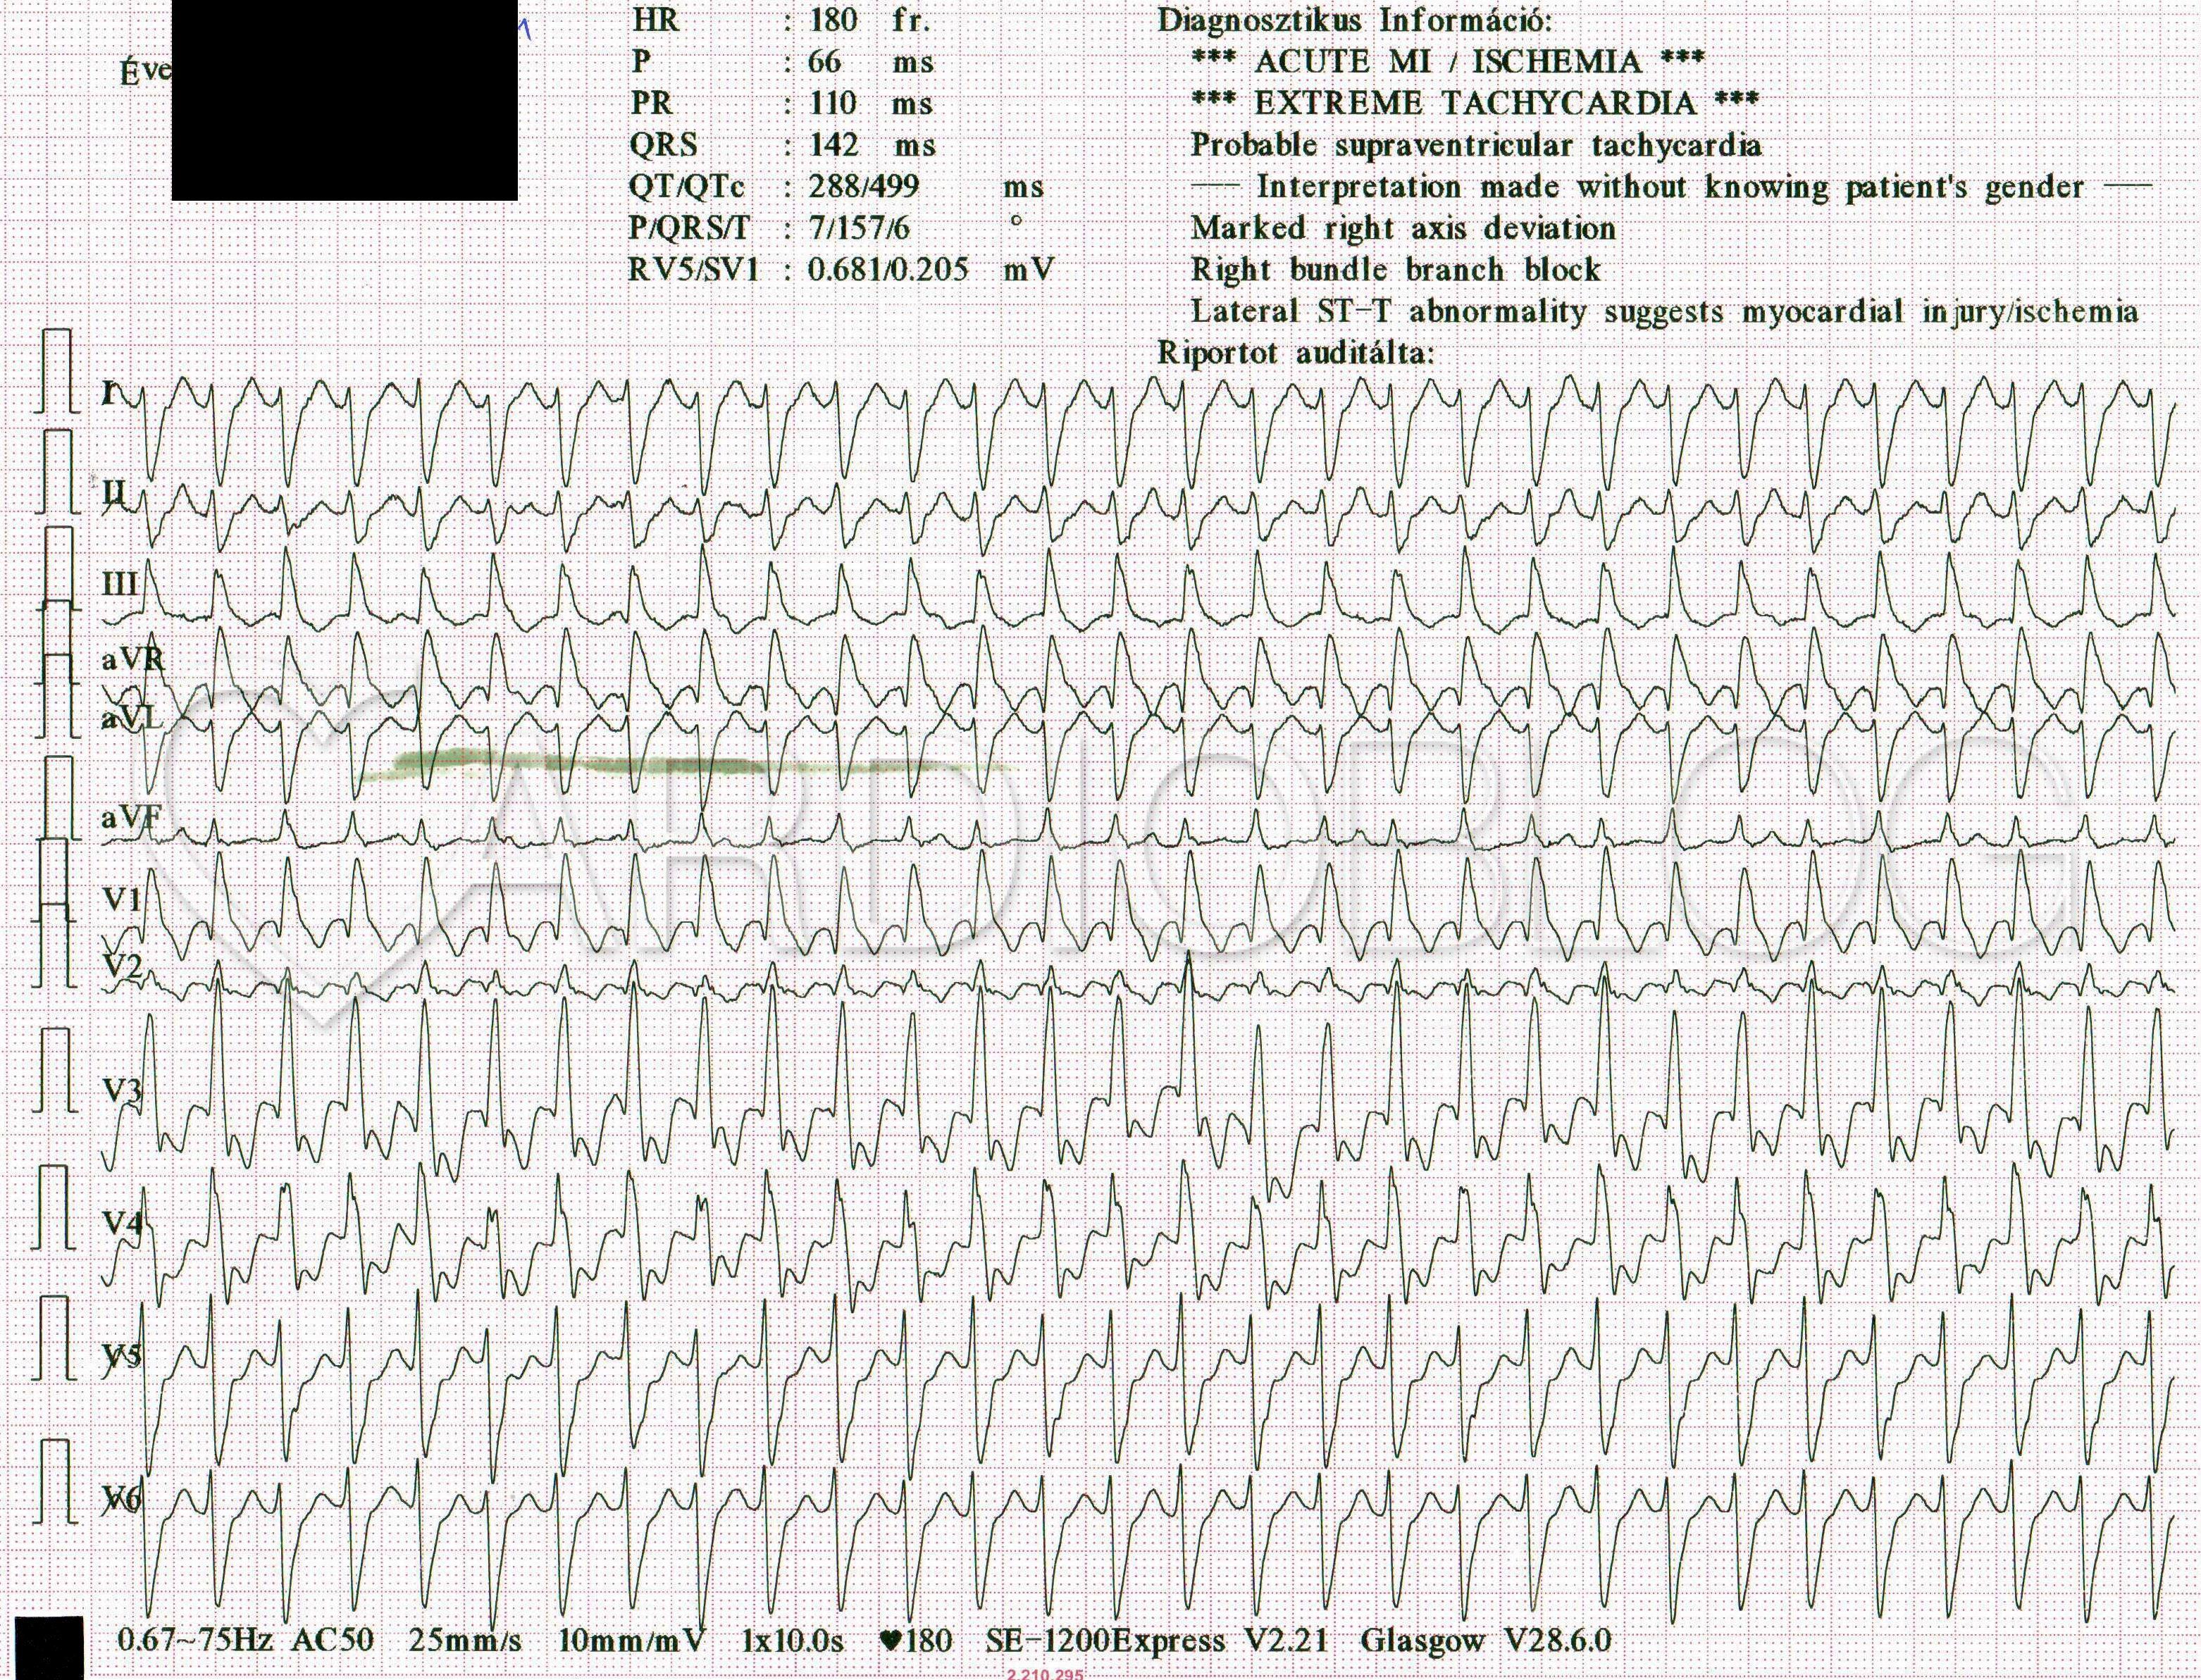

12-elvezetéses EKG az SBO-n:

A klinikum, a beteg életkora, strukturális szívbetegség hiánya és a QRS morfológia alapján JTSZB+ bal posterior fasciculus blokkal levezetett supraventricularis eredetű ritmuszavarra gondolhatnánk. Supraventricularis eredetre engedne következtetni a Vereckei algoritmus is, ha csak a QRS morfológiát vesszük alapul:

A V1-ben látható QRS is típusos jobb Tawara-szár-blokk és nem kamrai eredtre utal.

Az egyszerűsített Brugada kritérium szerint az utal kamrai tachycardiára, ha a II-es elvezetésben a QRS kezdetétől az első polaritásváltásig (tehát az R vagy a QS csúcsáig) eltelt idő több mint 50ms. Jelen esetben ez nem éri el a 40ms-ot sem.

Ha azonban a kályhától indulunk (ahogy kell) és keressük a P-hullámokat, hogy megpróbáljunk véleményt mondani a pitvar-kamrai aktiváció viszonyáról, akkor meg kell találnunk azt az elvezetést, ahol a P a legjobban látszik. Emlékeztetőül: a P mindig ott látszik a legjobban ahol kisebb a T-hullám (és/vagy a QRS), mert akkor ezek kevésbé takarják el.

Ha vettük a fáradságot és végignéztük az egész regisztrátumot, akkor a 12-elvezetéses EKG-n az aVF-ben fedezhettük fel talán a legjobban a P-hullámokat, melyek egyértelműen disszociáltak a QRS-ektől:

A kamrai tachycariák (VT) 10%-a idiopathiás, azaz nem társul strukturális szívbetegség. Az idiopathiás VT-k domináló többsége a jobb kamrai kiáramlási pályából ered. Csupán csak 10-15% ered a bal kamrából. Ezek közül a leggyakoribb a fascicularis kamrai tachycardia. Ez a ritmuszavar a fiatal (15-40 éves) generációra jellemző. 60-80%-ban férfiaknál jelentkezik. További jellegzetességei, hogy monomorf, relatíve keskenyebb QRS-sel jár, mint a többi kamrai tachycaria (100 – 140 ms) és típusos jobb Tawara-szárblokk morfológiát mutat (bal kamrai eredetű, ahol a QRS eleje gyors (meredek)).

- Anterior (az esetek 5-10%-a): jobb Tawara-szár-blokk+ bal posterior fasciculus blokk morfológia (extrém jobb deviáció). A reentry kilépési pontja a bal kamra anterolateralis falán található.